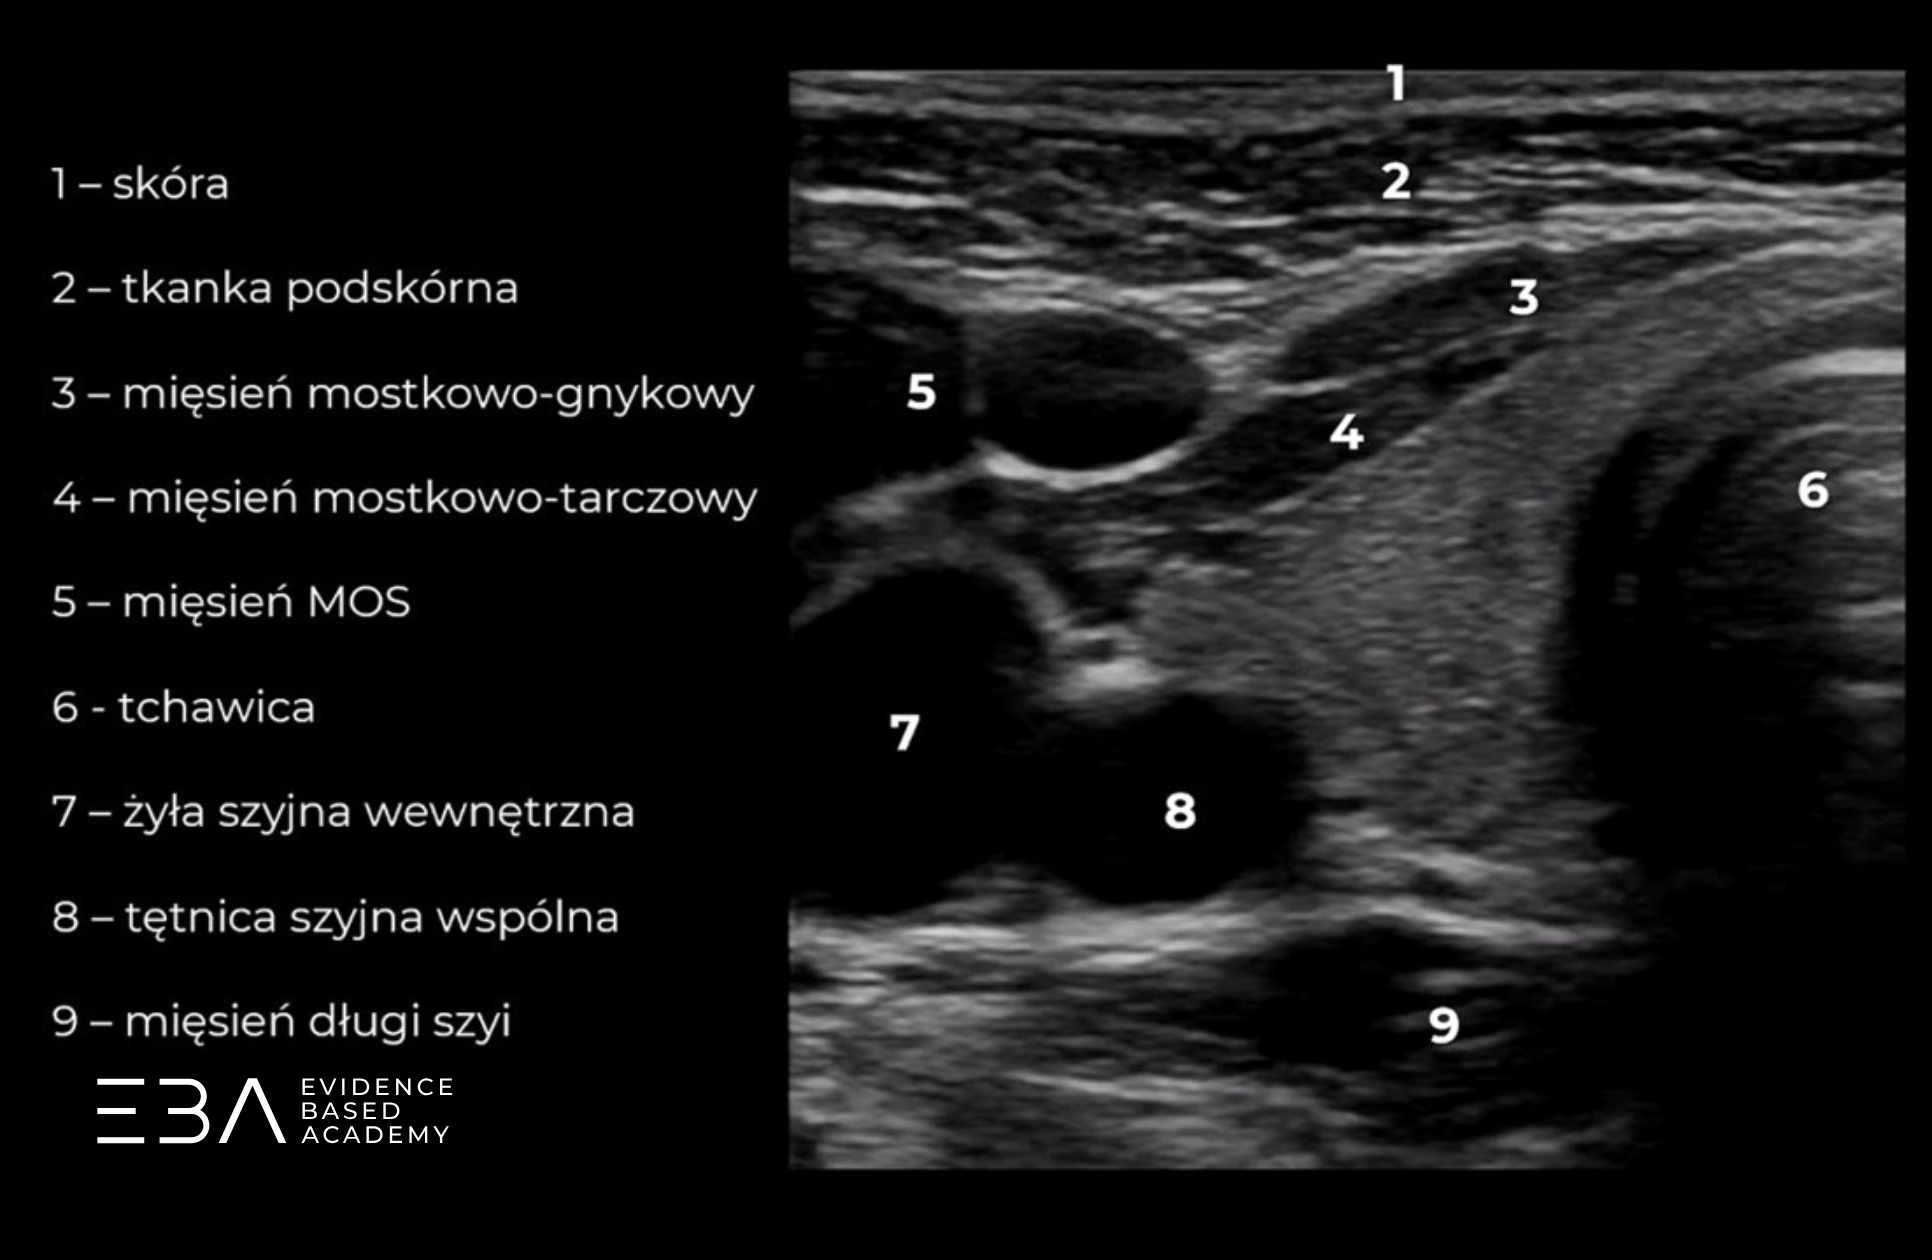

Projekcja poprzeczna z podpisami omawianych struktur.